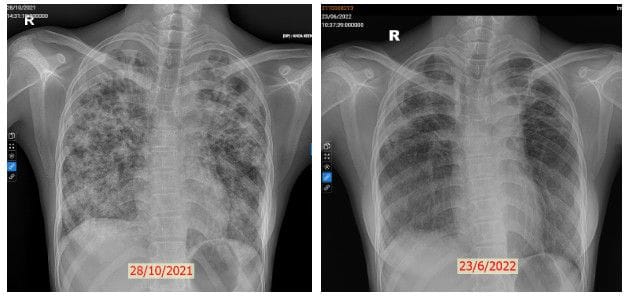

Nhân viên y tế tại khoa Lao Hô Hấp đã đón tiếp L.T.Q.M với tinh thần nhiệt tình và đảm bảo cô nhận được sự chăm sóc và điều trị tốt nhất. Quy trình chẩn đoán chính xác và kỹ thuật điều trị tiên tiến đã được áp dụng để đối phó với căn bệnh nặng nề của cô. Hình ảnh XQ ngực ban đầu cho thấy hai phổi của cô đã bị tổn thương toàn bộ, điều này phản ánh cô đã phải trải qua thời gian dài mắc bệnh mà không được phát hiện sớm. Các xét nghiệm vi sinh cũng đã khẳng định cô mắc bệnh lao phổi.

Sau 2 tháng nằm viện dài đằng đẵng và 6 tháng điều trị ngoại trú tại nhà, cô gái 17 tuổi đã trở lại với cuộc sống bình thường. Cô đã khỏi hoàn toàn căn bệnh lao phổi và sức khỏe của cô đã được phục hồi đáng kể. Từ chỗ không thể ngồi dậy, không thể tự thay quần áo, không thể tự thực hiện các hoạt động vệ sinh chăm sóc thân thể cơ bản hàng ngày, cô đã dần lấy lại được thể lực qua các bài tập phục hồi chức năng. Hiện tại, tổn thương phổi của cô đã tiến triển một cách thần kỳ, vi khuẩn lao không còn hoạt động, cô đã có thể đi bộ, chạy bộ như ngày trước. Đây không chỉ là chiến thắng của cá nhân cô mà còn là chiến thắng của tập thể khoa Lao Hô Hấp của Bệnh viện Phổi Trung Ương.